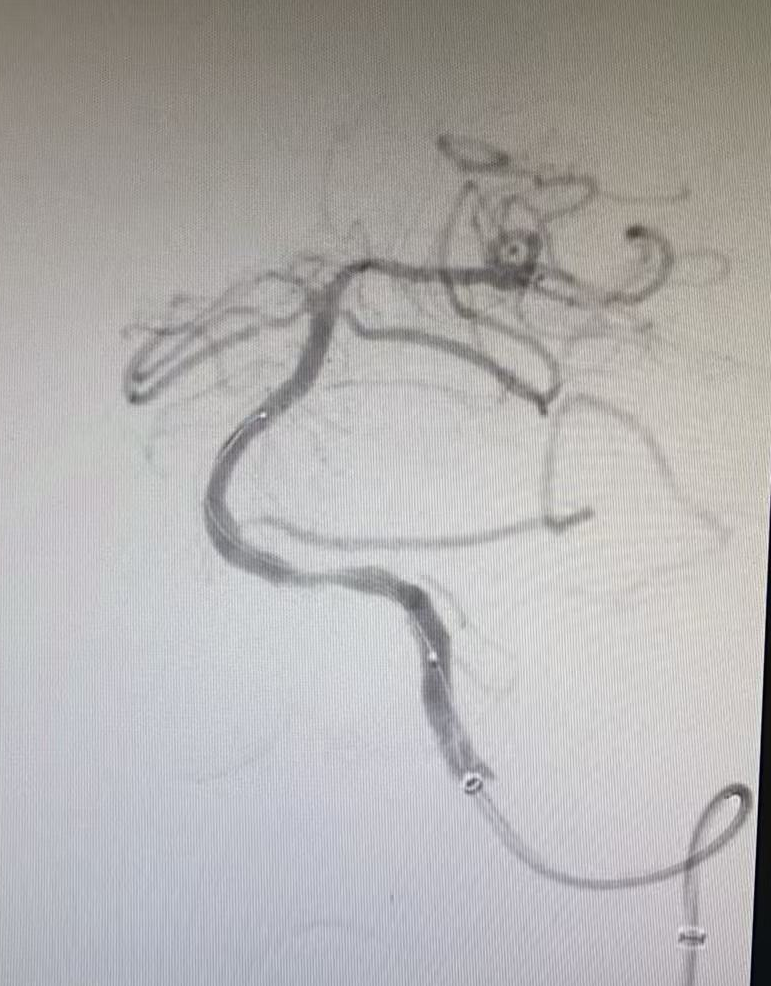

但挑戰(zhàn)還在繼續(xù),血管開通后發(fā)現(xiàn)內(nèi)部存在嚴(yán)重狹窄,遠(yuǎn)端血流灌注不足,團(tuán)隊(duì)隨即進(jìn)行球囊擴(kuò)張改善血流,但血管回縮明顯。為確保持久通暢,團(tuán)隊(duì)果斷植入一枚支架。最終,血管形態(tài)恢復(fù)良好,血流達(dá)到最佳標(biāo)準(zhǔn),缺血的大腦獲得了充足的血液供應(yīng)。

球囊擴(kuò)張術(shù)后